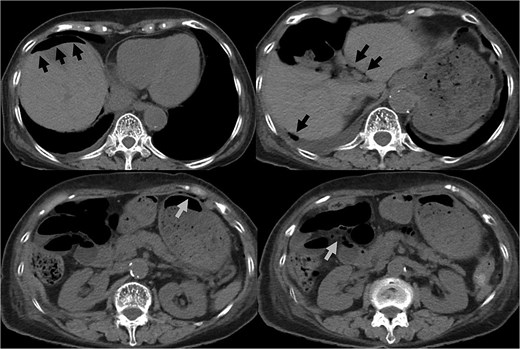

Coronal CT showed the urinary catheter was mispositioned outside the bladder (arrow).

The diagnosis of bladder rupture can be particularly challenging in cases with atypical presentations. In this patient, the presence of intra-abdominal air initially led to the suspicion of gastrointestinal perforation, although the mild abdominal tenderness was atypical for this condition. Retrospective analysis revealed that the urinary catheter had been mispositioned outside the bladder after penetrating the bladder wall, further complicating the clinical picture. This highlights the importance of considering bladder rupture in the differential diagnosis of patients with a history of pelvic irradiation presenting with intra-abdominal air and nonspecific symptoms.